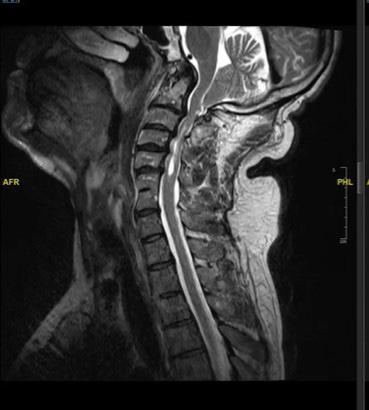

For nearly two years, Andrew Rosenberg experienced physical discomfort that was difficult to describe and even harder to diagnose. “I had an increasing sense of tingling and numbness in my left hand and fingers, and over time, my left arm began to feel very heavy when I would raise it,” he recounts. “I would also occasionally lose my balance and feel less steady on my feet. But no one could pinpoint what was wrong with me.”

The 56-year-old from Washington, D.C., underwent physical therapy and treatment for what his doctors thought might be a pinched nerve or carpal tunnel syndrome. Andrew was even tested for Parkinson’s disease. Still, his conditions persisted.

Last year, however, while undergoing an MRI to probe the source of shoulder pain he was enduring, Andrew had an epiphany. “I thought to myself ‘Why am I not getting images of my spine taken, too?’ It seemed like a logical thing to do.”

When his shoulder MRI revealed nothing concerning, Andrew’s doctor agreed to have his spine checked out at a well-regarded hospital in Washington, D.C. There, he was tested and diagnosed with Chiari malformation, a condition, usually present from birth, which occurs

when part of the skull is abnormally small or misshapen, putting pressure on the cerebellum, brain stem, and spinal cord. Throughout his life, that pressure had increased and was starting to block the flow of critical fluid, which cushions and surrounds the brain and spinal cord. Without surgery, Andrew’s condition would lead to a gradual paralysis of his arms and legs.

But this wasn’t all he faced.

In addition to the Chiari malformation, Andrew also had basilar invagination; a rare condition that occurs when the top of one’s spine presses into the base of the skull. In severe cases, like Andrew’s, the top of the spine compresses the brain stem and can cause neurological problems with a potentially fatal outcome.

Neurologists at Andrew’s Washington, D.C. hospital recommended that he undergo a brain decompression in addition to a total spinal fusion surgery to stabilize his spine permanently by fusing his skull and neck down to the L7 vertebra in his back; a procedure that would leave Andrew essentially unable to move his head.

A dad to two young kids, Andrew was hesitant to accept that option because of how it might negatively impact his quality of life. So, he continued to seek alternative

options and found his way to Johns Hopkins. There, he consulted with a world-renowned expert on spinal column biomechanics and surgical outcomes.

“The specialist at Johns Hopkins told me, that in his opinion, there were only two surgeons in the country with the expertise and creativity to do my surgery and potentially preserve my mobility,” Andrew remembers. “One was a former colleague of his who was practicing at Rhode Island Hospital, and he recommended that I see him as soon as possible.”

That colleague was Ziya Gokaslan, MD, Chief of Neurosurgery at Rhode Island Hospital, who was hyperresponsive to Andrew’s urgent situation; reviewing his images the day he received them and scheduling surgery within a week.

During the delicate, eight-hour surgery, Dr. Gokaslan removed a small section of bone in the back of Andrew’s skull, opening the covering of his brain, and sewed a patch in place to provide more room and help relieve the pressure. He also performed a fusion to align and stabilize his cervical spine to correct instability at the junction of his spine and skull, using screws, plates, and rods to bolster the compromised area.

“We limited the extent of Andrew’s fusion to preserve mobility,” Dr. Gokaslan explains, “and addressed his lifethreatening condition. His outlook is excellent and he’s very likely to make a full recovery.”